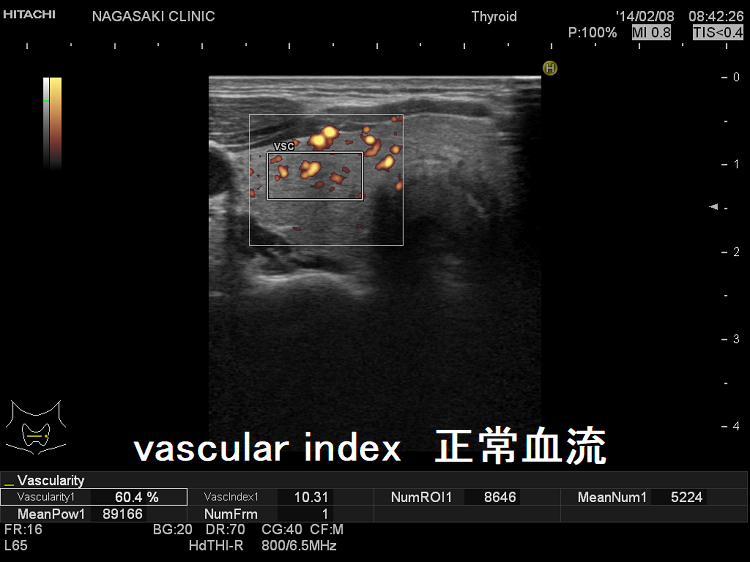

甲状腺内の血流評価 [%vascuralityまたはvascular index(血流指数)または血管密度]

甲状腺内の血流を定量評価[%vascuralityまたはvascular index(血流指数)または血管密度]

現在、vascular index(血流指数)の有用性を検証中です。甲状腺機能亢進症/バセドウ病甲状腺機能低下症無痛性甲状腺炎の回復期でも甲状腺内血流は増加し、少なくとも甲状腺ホルモンが正常範囲を外れているのを瞬時に予測できます。

vascular index 正常血流

vascular index 血流増加